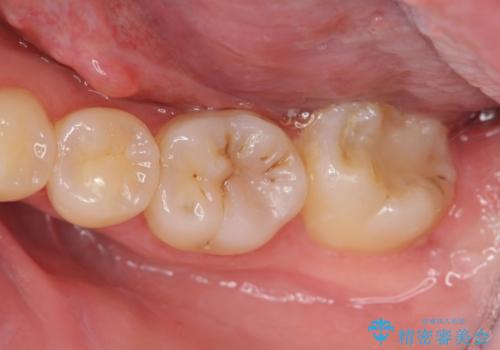

歯冠長の延長を行ったことで、安定したクラウン治療を行うことができました。

クラウン形態にするには歯の高さが足りず設計できないため、親知らずの抜歯と共に歯周外科を同時に行うことで安定した歯周組織を獲得しセラミック治療を行う治療計画としました。

- 20.9万円(ジルコニアクラウン・仮歯・セラミックインレー)費用は治療当時の料金となります